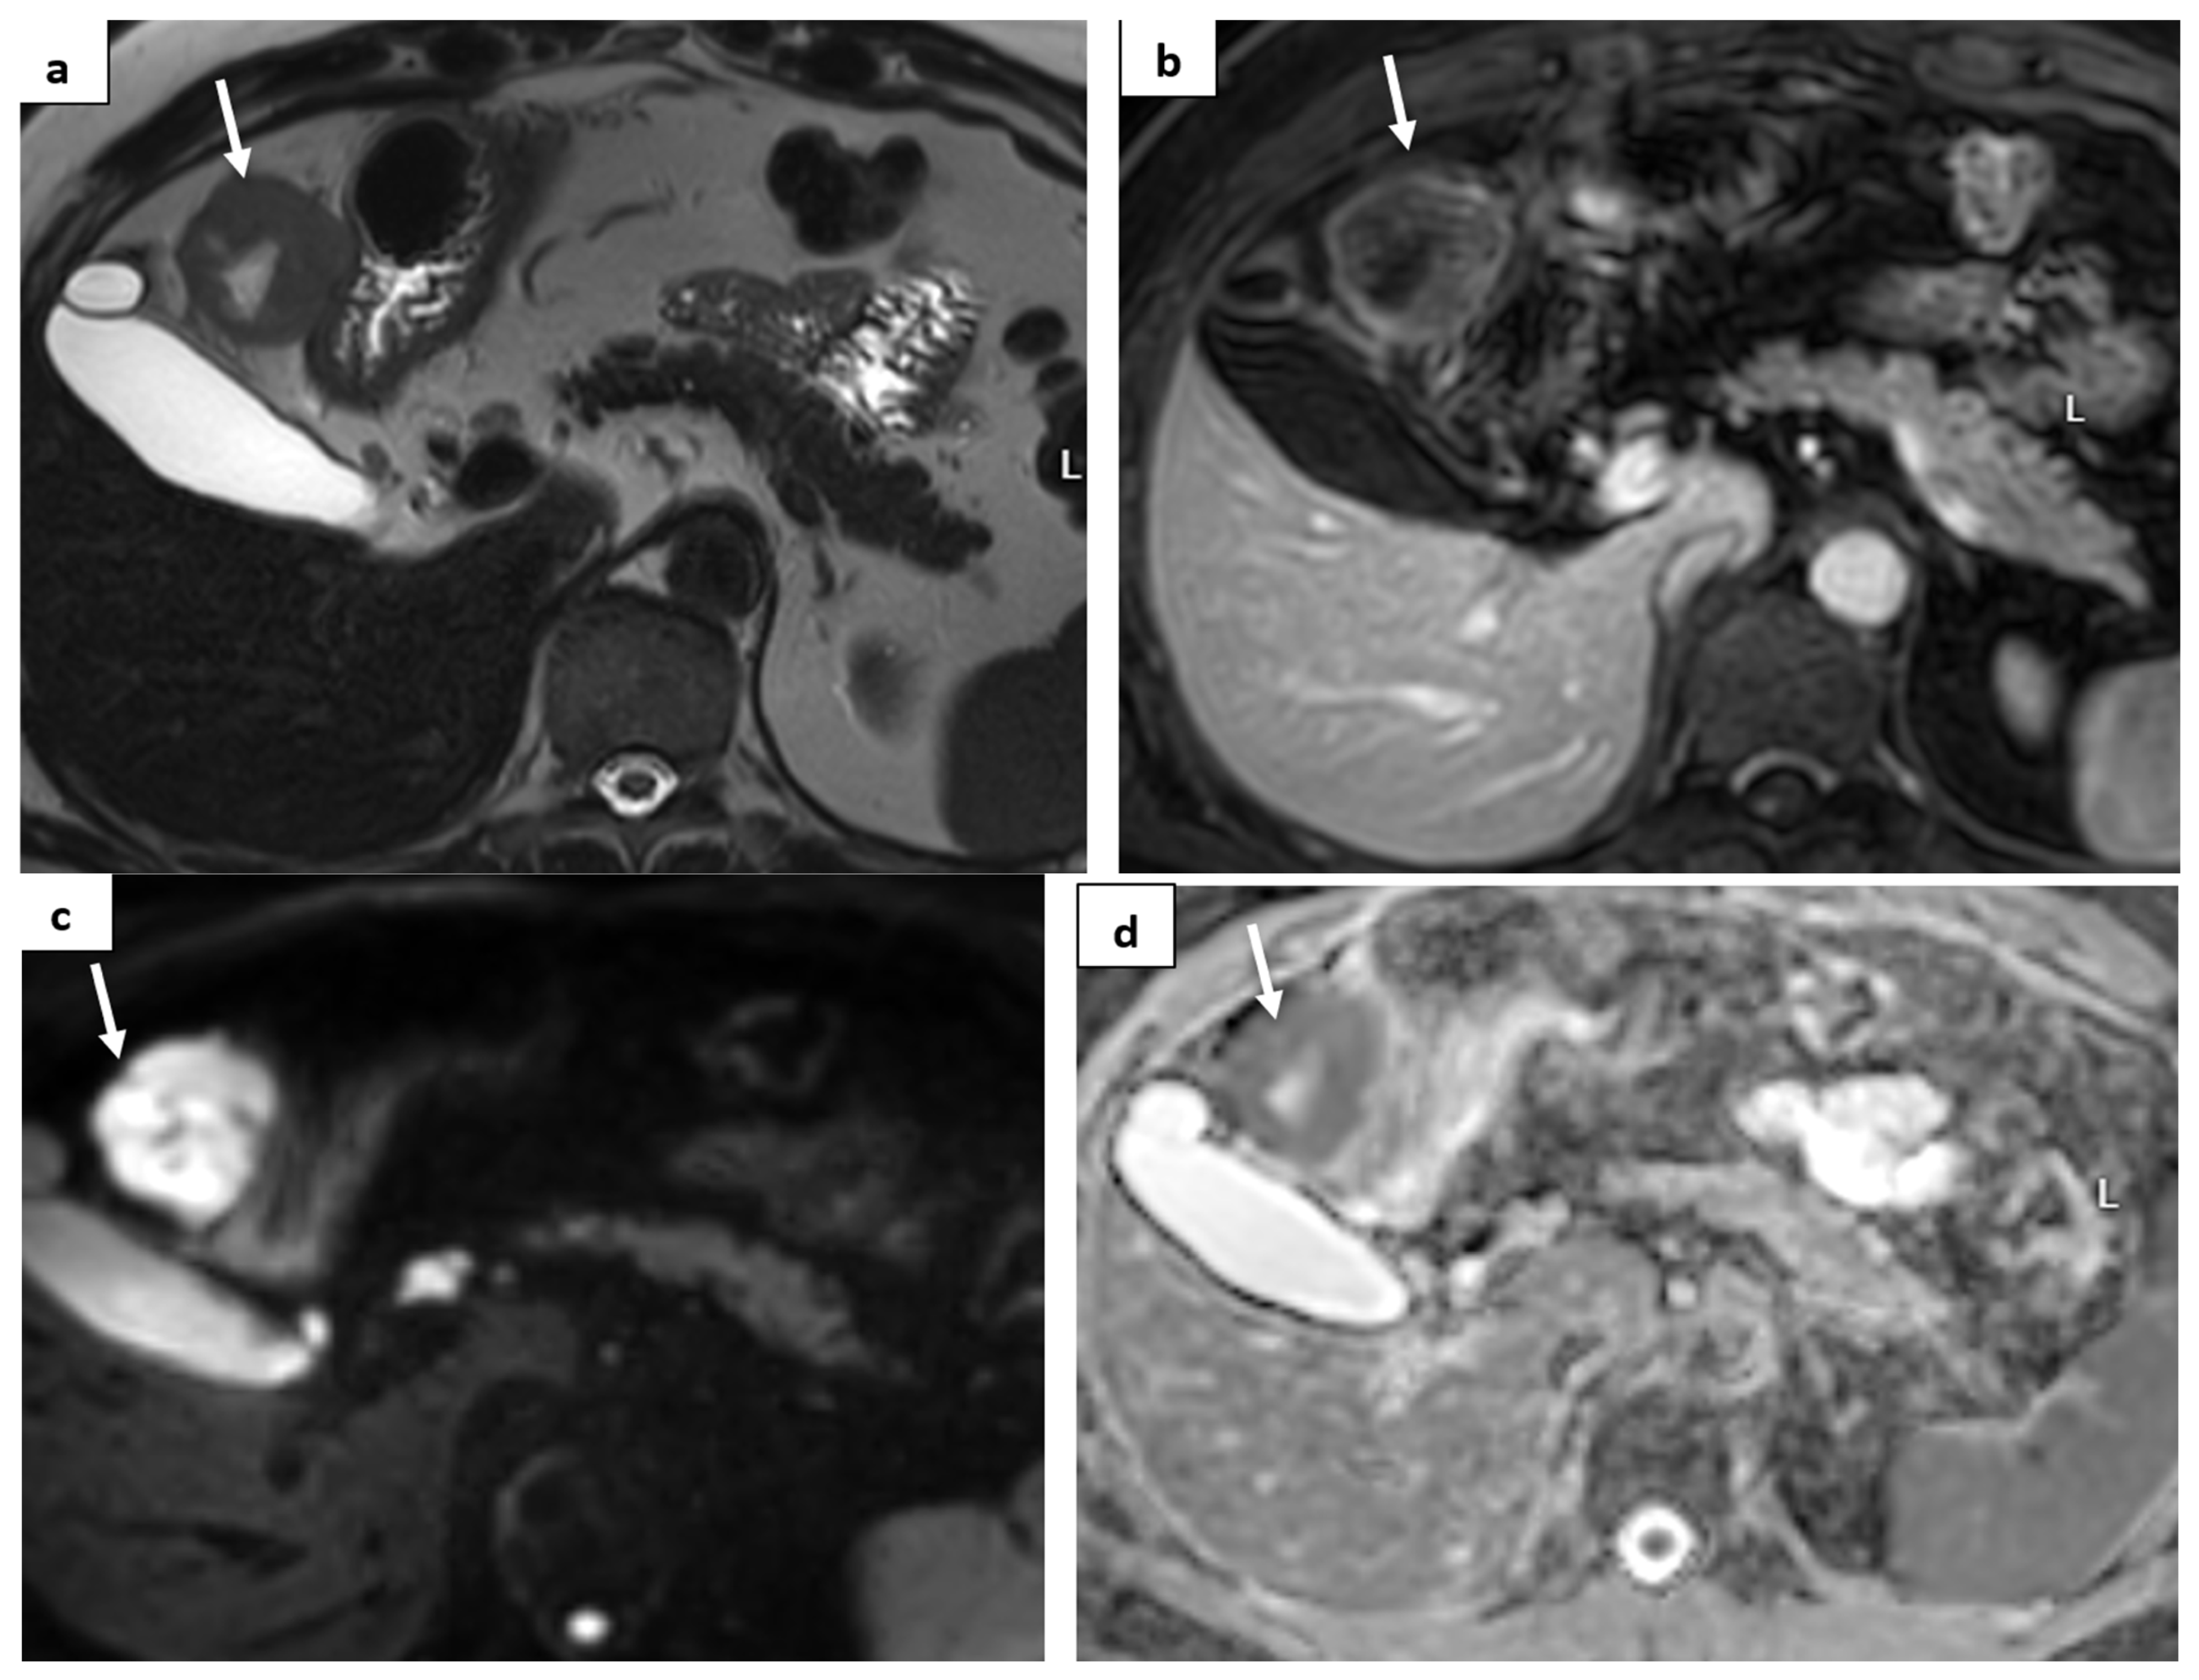

2. Case Report